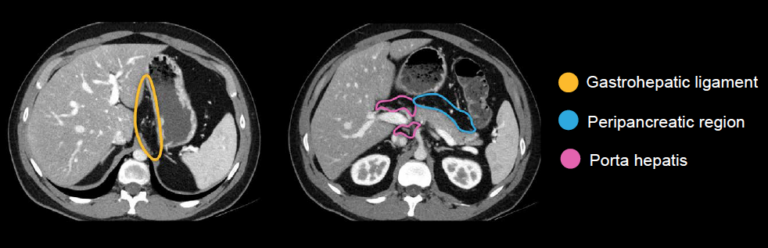

Porta Hepatis Lymph Node

animalia-life.club

animalia-life.club

Abdominal CT: Lymph Nodes • LITFL • Radiology Library

litfl.com

litfl.com

Abdominal CT: Lymph Nodes • LITFL • Radiology Library

litfl.com

litfl.com